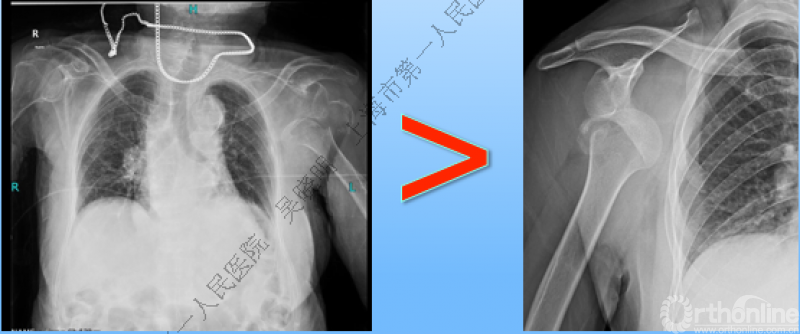

警惕喙突下老年性肩关节前脱位

肩关节内移程度与创伤暴力大小有关

喙突内脱位                              肩胛盂下脱位

必要时进一步CT检查

特别警惕伴肱骨头外翻合并大结节骨折的肩关节脱位

警惕:有无肱骨头外翻

肩关节前脱位伴大结节骨折:颈干角正常

无肱骨头外翻伴大结节骨折的老年性肩关节前脱位

Neer 分型:二部分大结节骨折脱位:手法复位

伴大结节骨折的老年性肩关节前脱位伴肱骨头外翻

肩关节前脱位合并大结节骨折&肱骨头外翻:外翻压缩型(Neer 分型)

对这型骨折进行手法复位会导致肱骨头和肱骨干之间的连续性消失。肱骨头和肱骨干之间连续性尚存,肱骨头前脱位(Robsion 3b)